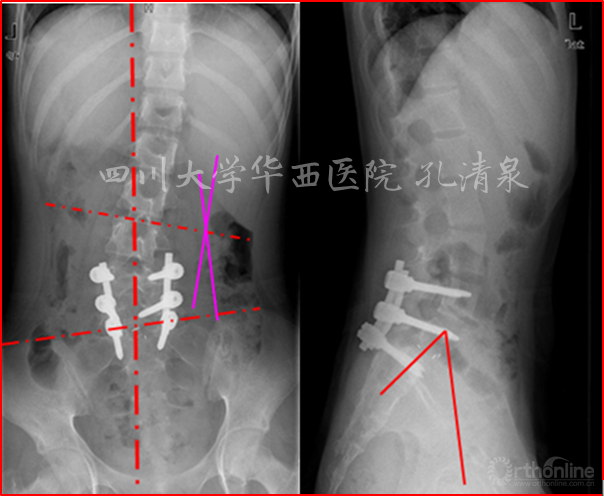

图1 术前X线示:腰5椎IV度滑脱并脊柱侧凸,颈胸弯中立位16°,减轻位0°,胸弯中立位50°,减轻位12°,腰弯33°,减轻位5°,均为非结构性弯。

图2 侧弯的左右bending位摄片及腰骶部CT的矢状面重建及表面重建

图8 腰椎正位像上示多节段腰椎右侧横突骨折,腰骶部侧凸,CT矢状面重建示腰5椎IV°滑脱,腰5骶1椎间盘完好,骶1前上缘骨骺向前滑移